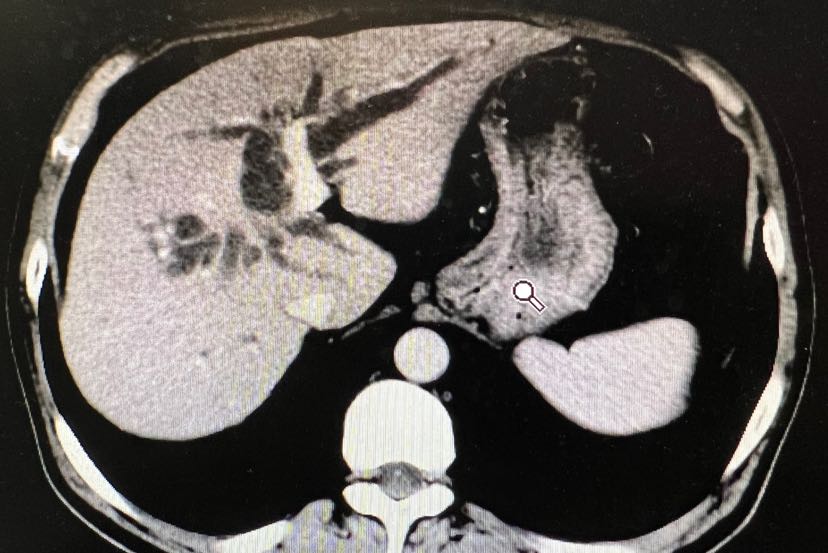

胆管癌手术前要不要做胆道引流

图片尺寸828x553

行左肝ptcd胆道穿刺引流减黄保肝治疗,引流1月后左肝胆管扩张缓解

图片尺寸1080x1440